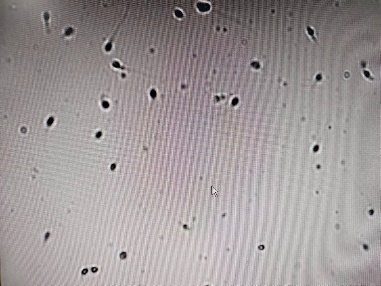

第二是看精子活力。精子向前运动的能力,是直接反映精子质量的一项指标。WHO将活力分3级:前向运动(PR):精子主动地呈直线或沿一大圆周运动,不管其速度如何。非前向运动(NP):所有其他非前向运动形式,如以小圆周泳动,尾部动力几乎不能驱使头部移动,或者只能观察到尾部摆动。不活动(IM):没有运动。正常情况下射精60min内,PR级精子应>32%;或PR和NP级精子之和大于40%就可以了。精子活力低提示可能有炎症、性激素水平低或弱精子症等疾病。